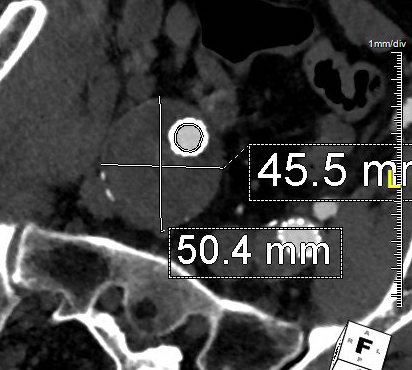

The patient is a man in his sixties with hypertension who presented with a 4.7cm AAA which in various reports he came with described 5.2×4.7cm. After review of his images, it was clear it was 4.7cm. If measured on a typical axial cut CT scan or a horizontally oriented ultrasound probe, a cylindrical aortic aneurysm will be seen as an ellipse in cross section. A radiology report will typically report an aneurysms length and the anteroposterior and lateral dimensions. If you cut a sausage at an angle, the ovals you cut can be quite wide but the smaller length of the oval reflects the diameter of the sausage.

Looking back at his records, for three years he had multiple CT scans for abdominal  pain showing the AAA and a well documented record of growth of about 2-3mm annually -the normal growth rate. He asked me to prognosticate and so I relayed that 4.7cm in 2017 with a 3mm growth rate, we would be operating in 2020. The anatomy was favorable with a long infrarenal neck and good iliac arteries for distal seal and access. He was quite anxious as whenever he had abdominal pain, his local doctors would discuss the AAA and its risks or order a CT. After a long discussion and considerable lobbying by the patient and family, I agreed to repair his 4.7cm AAA.

The EVAR was performed percutaneously. No endoleak was detected by completion arteriography (figure). He was soon discharged and was grateful. In followup, CT scan showed excellent coverage of the proximal and distal zones and absence of type III endoleaks. There was increased density to suggest a type II leak, but his inferior mesenteric artery was not the source of it. over a three year period, his aneurysm sac continued its 2-3mm of annual growth despite the presence of the the stent graft.

Three years of followup showed growth of the AAA sac to 5.5cm, which ironically threshold for repair. Again, no type I or III endoleak could be seen. He reached his calculated repair date, and I discussed our options in detail.